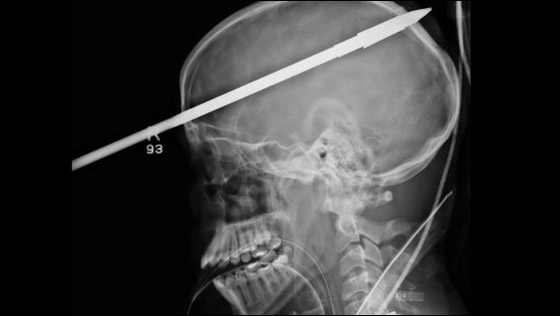

لعبت معجزة حقيقية دورها في نجاة مراهق أميركي من موت مؤكد، وذلك بعد أن اخترق رمح جمجمته. وأظهرت صور أشعة سينية كيف اخترق رمح الصيد رأس المراهق ياسر لوبيز (16 عاماً) الذي تعرض إلى ذلك الحادث خلال ممارسته هواية السباحة في بحيرة قريبة من بلدة ميامي- ديد التابعة لولاية فلوريدا.

ووفقاً لما أوردته صحيفة أميركية فإن الرمح الطائش انفلت من صياد أسماك بالخطأ وانطلق ليستقر في جبهة المراهق مخترقاً جزءاً من رأسه قبل أن يبرز جزء منه من الجانب الخلفي من الرأس. وقال الأطباء الذين أسعفوا المراهق المحظوظ انه نجا من الموت بأعجوبة، إذ ان الرمح لم يتسبب في تمزيق أي شرايين أو مراكز حيوية في المخ، منوهين إلى أن لوبيز يتعافى حاليا بشكل جيد ومبشر في مستشفى جاكسون ميموريال. ونقلت الصحيفة عن أحد الأطباء قوله: "انها معجزة حقيقية كون الرمح لم يمزق الأوعية الدموية الرئيسية في المخ"، مشيراً إلى ان عملية استخراج الرمح كانت صعبة جداً لكنها تكللت بالنجاح بعد 3 ساعات من الجهود الجراحية المتواصلة. لكن الأمر الذي يقلق الأطباء حالياً هو أن المراهق المصاب لا يستطيع أن يتذكر ما حصل، وهو ما ينذر بأنه ربما يكون قد أصيب بفقدان جزئي أو كلي للذاكرة.